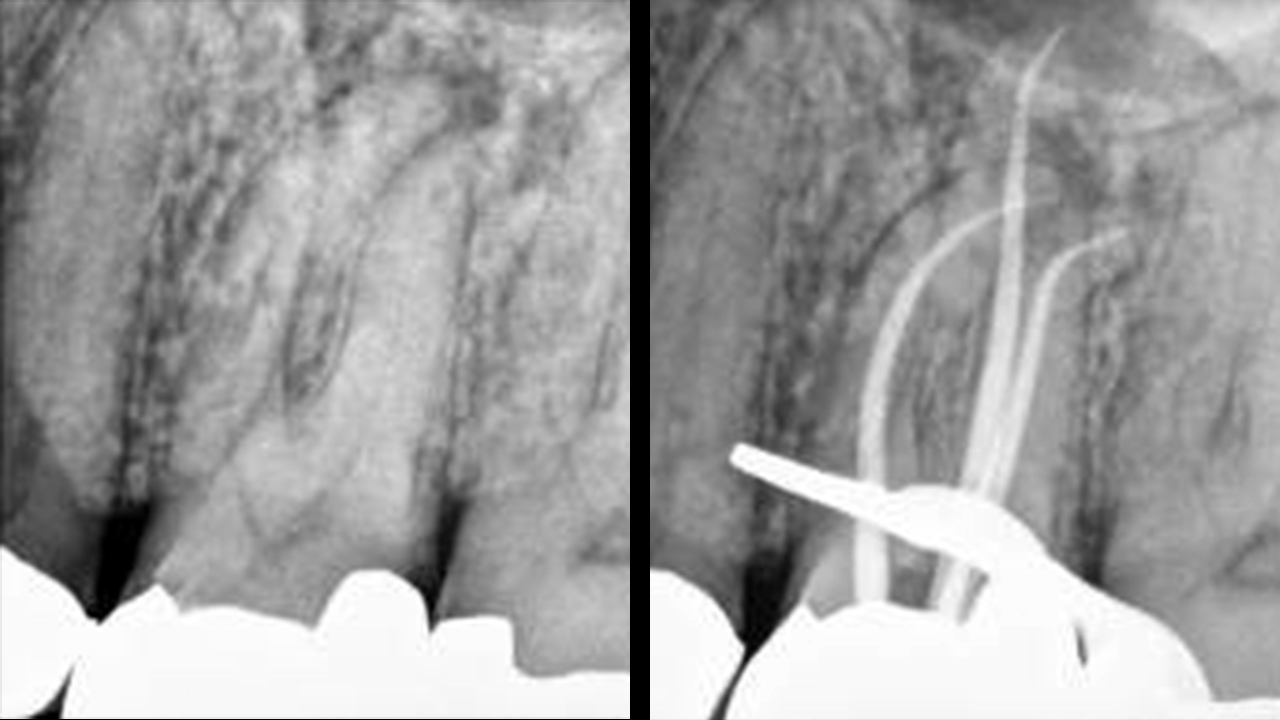

A clinical example of 3 successful conefits to be easily followed by predictable 3-D obturation.

Introduction “The pulp is a big issue about a little tissue.” This quote is credited to early endodontic educator Dr. Sam Seltzer of Philadelphia. Nothing has changed. Restorative dentists have discovered that endodontics is one of the fastest ways to grow their practices, and, therefore, most dentists want to add more endodontic procedures to their … Read more